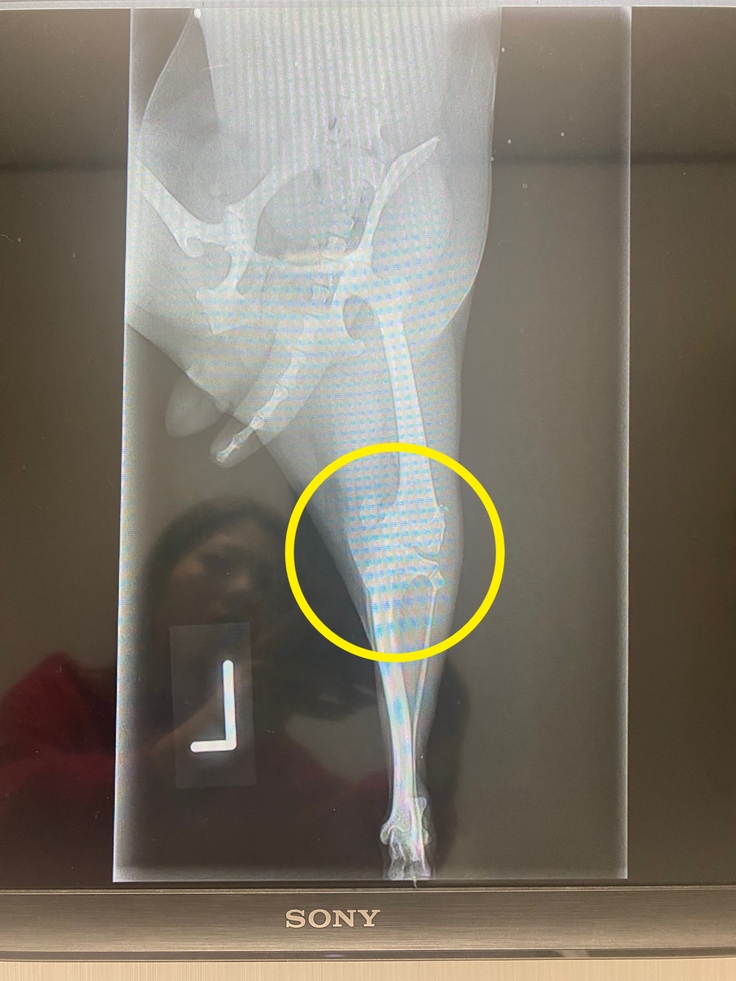

右後ろ足を上げて両手と左後ろ足で歩くのが日常茶飯事だったのですが特に痛がる様子もなく日々毎日を過ごしていたのですが、今年の7月頃ふとあんずを見てみると両足を引きずったような歩き方をしていてとても不安になりすぐ動物病院に連れて行ったところ、『両足とも膝蓋骨脱臼してるね。このままだと将来歩けなくなる可能性があるからすぐにでも手術をしてあげたほうが良い』と言われ目の前が真っ暗になったのを今でも覚えています。そしてすぐに手術が可能な別の動物病院を紹介していただきました。

長距離の移動もストレスを与えてしまうと思い翌日に紹介していただいた病院へ連れて行ってみると『100%治ると断言はできないがこれから先10年、15年一緒に暮らしていくのを考えるとすぐにでも手術した方がいいし、今よりも格段に良くなるのは保証できる』と心強いお言葉をいただき、右後ろ足の膝蓋骨脱臼の手術をすることを決断しました。

その後手術は無事成功し数ヶ月の安静期間を経て現在は普通に右後ろ足を使えるようにまでなりました。そしていよいよ今月が左後ろ足の手術です。こちらも右後ろ足同様膝蓋骨脱臼G4の重度であるため、膝蓋骨脱臼整復・大腿骨骨切(大腿骨短縮、部分骨切除)の手術を行わなければなりません。大きい手術のため費用もかなりかかります。ですが、両足の痛みもなくなり少しでも今以上に大好きな外を走り回ったり沢山お散歩に行けるようになるなら後悔なく手術を受けさせてあげたいと思いこのプロジェクトを立ち上げました。

2023年11月8日に左後ろ足の膝蓋骨脱臼の手術を行います。1週間前後の入院予定期間を経て退院後、まずは1週間後の経過観察。その後、3週間おきに3回ほど通院すれば治療完治となる予定です。動物保険適用のため約24万円の保険金が出ますが、退院後の検診や治療費などで完治までに自己負担金が50万円ほど必要になると予想されます。手術の一部費用と治療代の10万は自分達でどうにか用意します。残りの40万のあんずの手術入院術後の医療費を皆様のお力をお借りして助けて頂きたいです。どうかよろしくお願いいたします。

○治療・手術内容

左後ろ足膝蓋骨脱臼G4整復術

大腿骨骨切術(大腿骨短縮術/部分骨切除術)